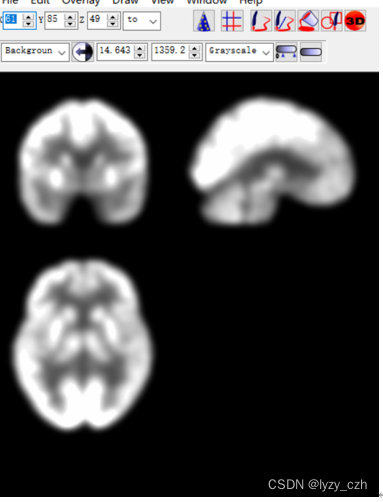

使用MRIcron打开hdr文件如下:MRIcron在我的之前的文章有介绍

打开output图像如下:

最后得到的图像如下: